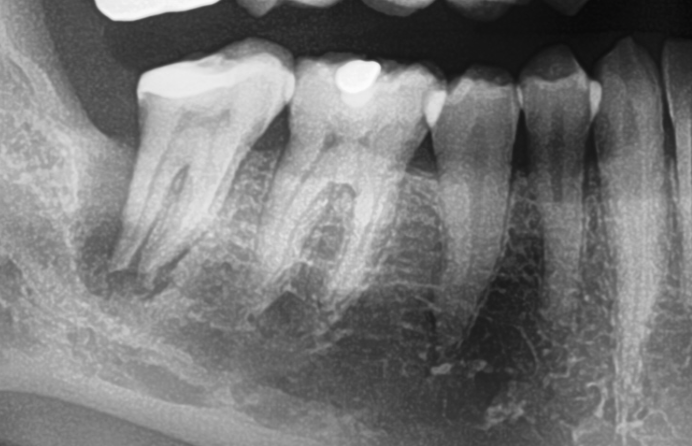

Screenshot 2016-05-16 19.35.54 Veröffentlicht 16. Mai 2016 am 692 × 446 in Starker distaler Knocheneinbruch – Lohnt der Versuch eines Zahnerhaltes ?